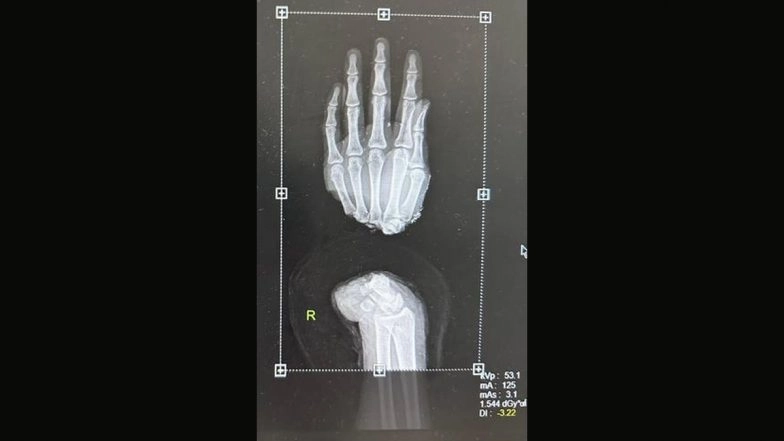

New Delhi, April 17: In yet another medical marvel, doctors here have restored the right hand of a 28-year-old daily wage labourer who lost his limb to an accident. Delhi-based Ashok faced a terrible accident at his work site in Bawana on April 7. As a result, his right hand became completely detached.

The team of doctors at Sir Ganga Ram Hospital in a complex eight-hour surgery worked swiftly to reunite the broken bones, tendons, nerves, arteries, and veins that had been cut during the accident. Delhi: Man Undergoes Surgery to Remove 39 Coins, 37 Magnets from Intestine at Sir Ganga Ram Hospital.

"It took us eight hours to completely reattach his right hand, and the patient was discharged after 5 days of monitoring with the hand doing good, and the patient in a stable condition," Nikhil said.